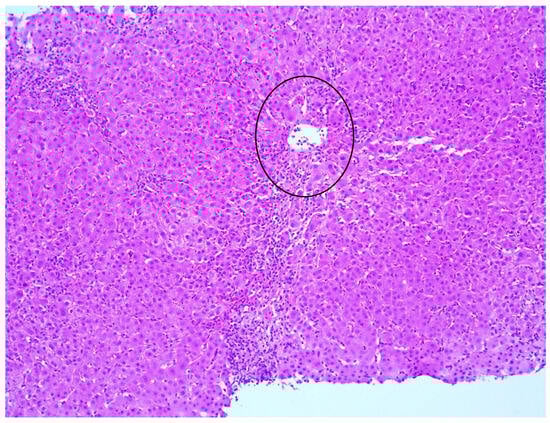

| Clinical Characteristics | Interface Hepatitis (Figure 1) | Lym | Plasmacells (Figure 2) | Eos | PAS-pos MP | Centrilobular Necrosis (Figure 3) | Emperipolesis | Rosettes | Ductular Reaction | Fibrosis | AIH Score |

|---|---|---|---|---|---|---|---|---|---|---|---|

| 1. Female, 36 | Moderate, focal | Yes | Moderate | Yes | No | Yes | No | Yes | Minimal bile ducts neogenesis | Yes | 19 |

| 3. Male, 14 | Mild, focal | Yes | Mild | Yes | Yes | Yes | No | No | Bile ducts neogenesis, ductal metaplasia | Yes | 15 |

| 4. Female, 44 | Moderate, focal | Yes | Mild | No | Yes | Yes | No | No | Minimal bile ducts neogenesis | Yes | 17 |

| 5. Male, 61 | Moderate | Yes | Moderate | Yes | Yes | Yes | No | No | No | Yes | 16 |

| 7. Male, 46 | No | No | No | No | Yes | No | No | No | No | No | 3 |

| 8. Female, 65 | Mild, focal | Yes | Few | Yes | Yes | No | No | No | No | No | 11 |